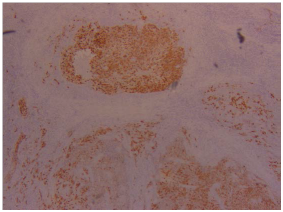

The pathology report revealed presence of lymphoepithelial carcinoma of the right parotid gland with positive lymph nodes from specimens taken. Upon performing pathological studies, the sample excised was stained with hematoxylin and eosin stain (Figure 3) which showed lymphocytic infiltrates invading the parotid gland, EBER stain (Figure 4) showed positive results for presence of Epstein bar virus. The excised lymph nodes were also stained (Figure 5), and metastasis was found.

Figure 4 EBER stain showing Epstein Bar Virus positive.